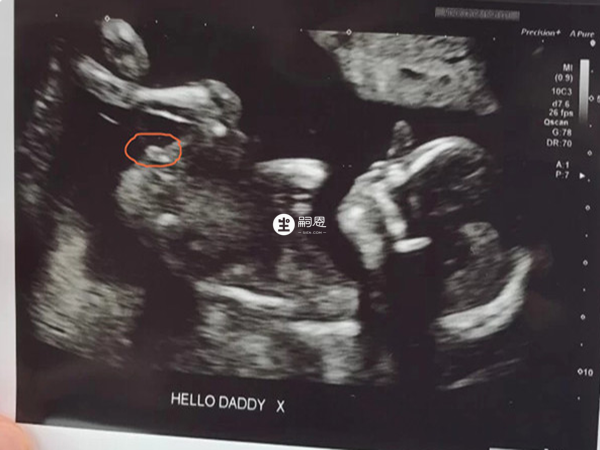

在NT單子上會有寶寶的影象,可以看到如果影象上男孩的特徵點與身體呈45度角,並且屁股位置微微上翹,後背脊柱成圓弧狀,那麼暗示可能是男孩,如果影象上胎兒的尾椎骨和軀體平行,後背脊柱相對平一些,那麼暗示可能是女孩。

很多都說nt結果暗示男女,主要看的是nt值以及nt影象胎兒的特點,nt值大於1.5,生男孩可能性大,反之生女孩多。nt影象如果胎兒特徵點與身體呈45度角,可能是男孩,如果是平行的,可能是女孩,也有人說通過三個點能看出男孩女孩,但其實哪種說法都不準確,因為孩子性別與此無關。